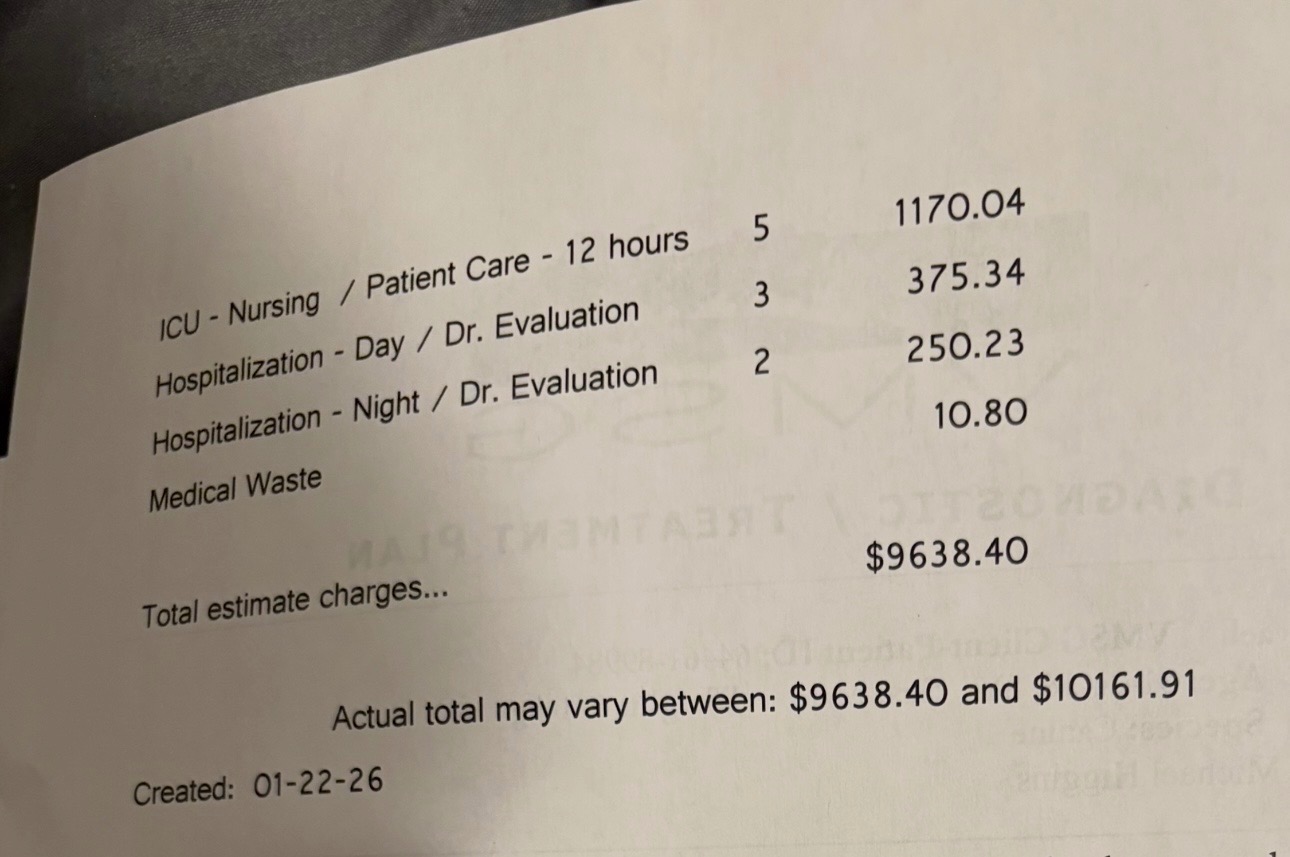

The total estimated cost for Chompers’ emergency care and spinal surgery is $10,161.91, based on official hospital estimates and invoices. This includes emergency care, advanced imaging, neurology consultation, surgery, anesthesia, ICU recovery, medications, and post-operative care. I am attaching all medical records and invoices for full transparency.